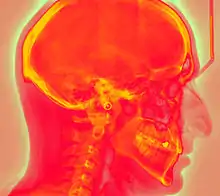

Projectional radiography using a photostimulable phosphor plate as an X-ray detector can be called "phosphor plate radiography"[1] or "computed radiography"[2] (not to be confused with computed tomography which uses computer processing to convert multiple projectional radiographies to a 3D image).

In phosphor plate radiography, the imaging plate is housed in a special cassette and placed under the body part or object to be examined and the x-ray exposure is made. The imaging plate is then run through a special laser scanner, or CR reader, that reads and converts the image to a digital radiograph. The digital image can then be viewed and enhanced using software that has functions very similar to other conventional digital image-processing software, such as contrast, brightness, filtration and zoom. CR imaging plates (IPs) can be retrofitted to existing exam rooms and used in multiple x-ray sites since IPs are processed through a CR reader (scanner) that can be shared between multiple exam rooms.[6]